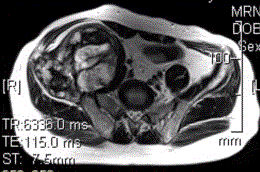

患者男,28岁,右下腹及臀部疼痛5个月余。查体:右髂骨外后侧压痛,右下腹可触及一软组织包块,质韧,固定。行骨盆正位CR、骨盆CT及MR扫描见下图。...

问题 患者男,28岁,右下腹及臀部疼痛5个月余。查体:右髂骨外后侧压痛,右下腹可触及一软组织包块,质韧,固定。行骨盆正位CR、骨盆CT及MR扫描见下图。 此病变最可能的诊断是

选项 A.骨囊肿 B.动脉瘤样骨囊肿 C.骨结核 D.骨巨细胞瘤 E.硬韧带样纤维瘤

答案 B